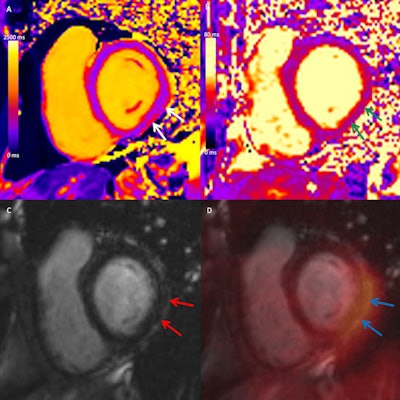

At two-month follow-up, PET/MRI showed evidence of myocardial inflammation in two of 17 participants diagnosed with acute myocarditis early after COVID-19 vaccination. The researchers found no myocardial edema or functional impairment in symptomatic or asymptomatic participants who did not meet the criteria for myocarditis early after vaccination.

Although there is no clear consensus on the optimal timing of follow-up imaging in patients with acute myocarditis, based on the additional PET metabolic findings in this study, the authors suggest the diagnostic yield of cardiac MRI more than two months after vaccination is likely low in individuals who do not have objective early signs of myocarditis.